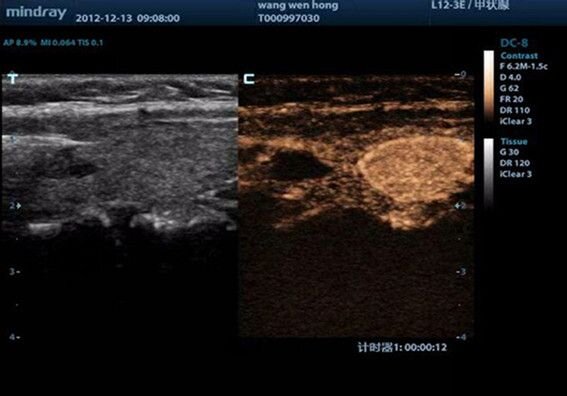

Mindray L12-3E УЗИ датчик

Цена по запросу